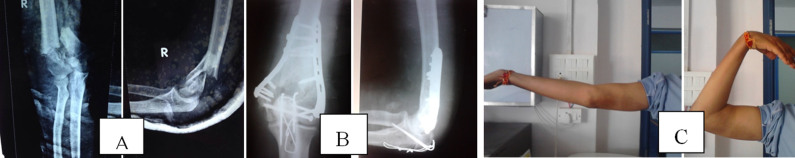

显示术前(A)和术后(B)X射线和临床图像(C)显示运动范围。